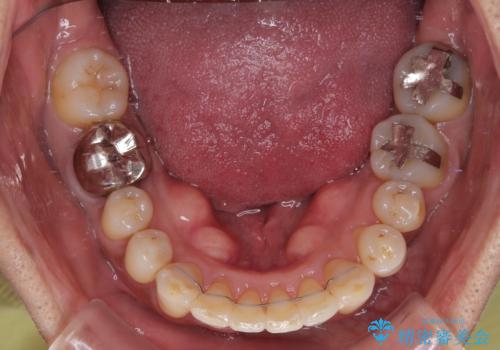

- 八重歯を気にして来院された患者様です。

上顎前歯の突出感と右上の八重歯を気にされていたので、上顎左右の第一小臼歯2本を抜歯し、ワイヤー装置にて矯正治療を行うこととしました。

上顎前歯に装着されていた保険診療の前歯は見た目が気になるとのことであったので、矯正治療後にオールセラミッククラウンにて補綴治療を行うこととしました。